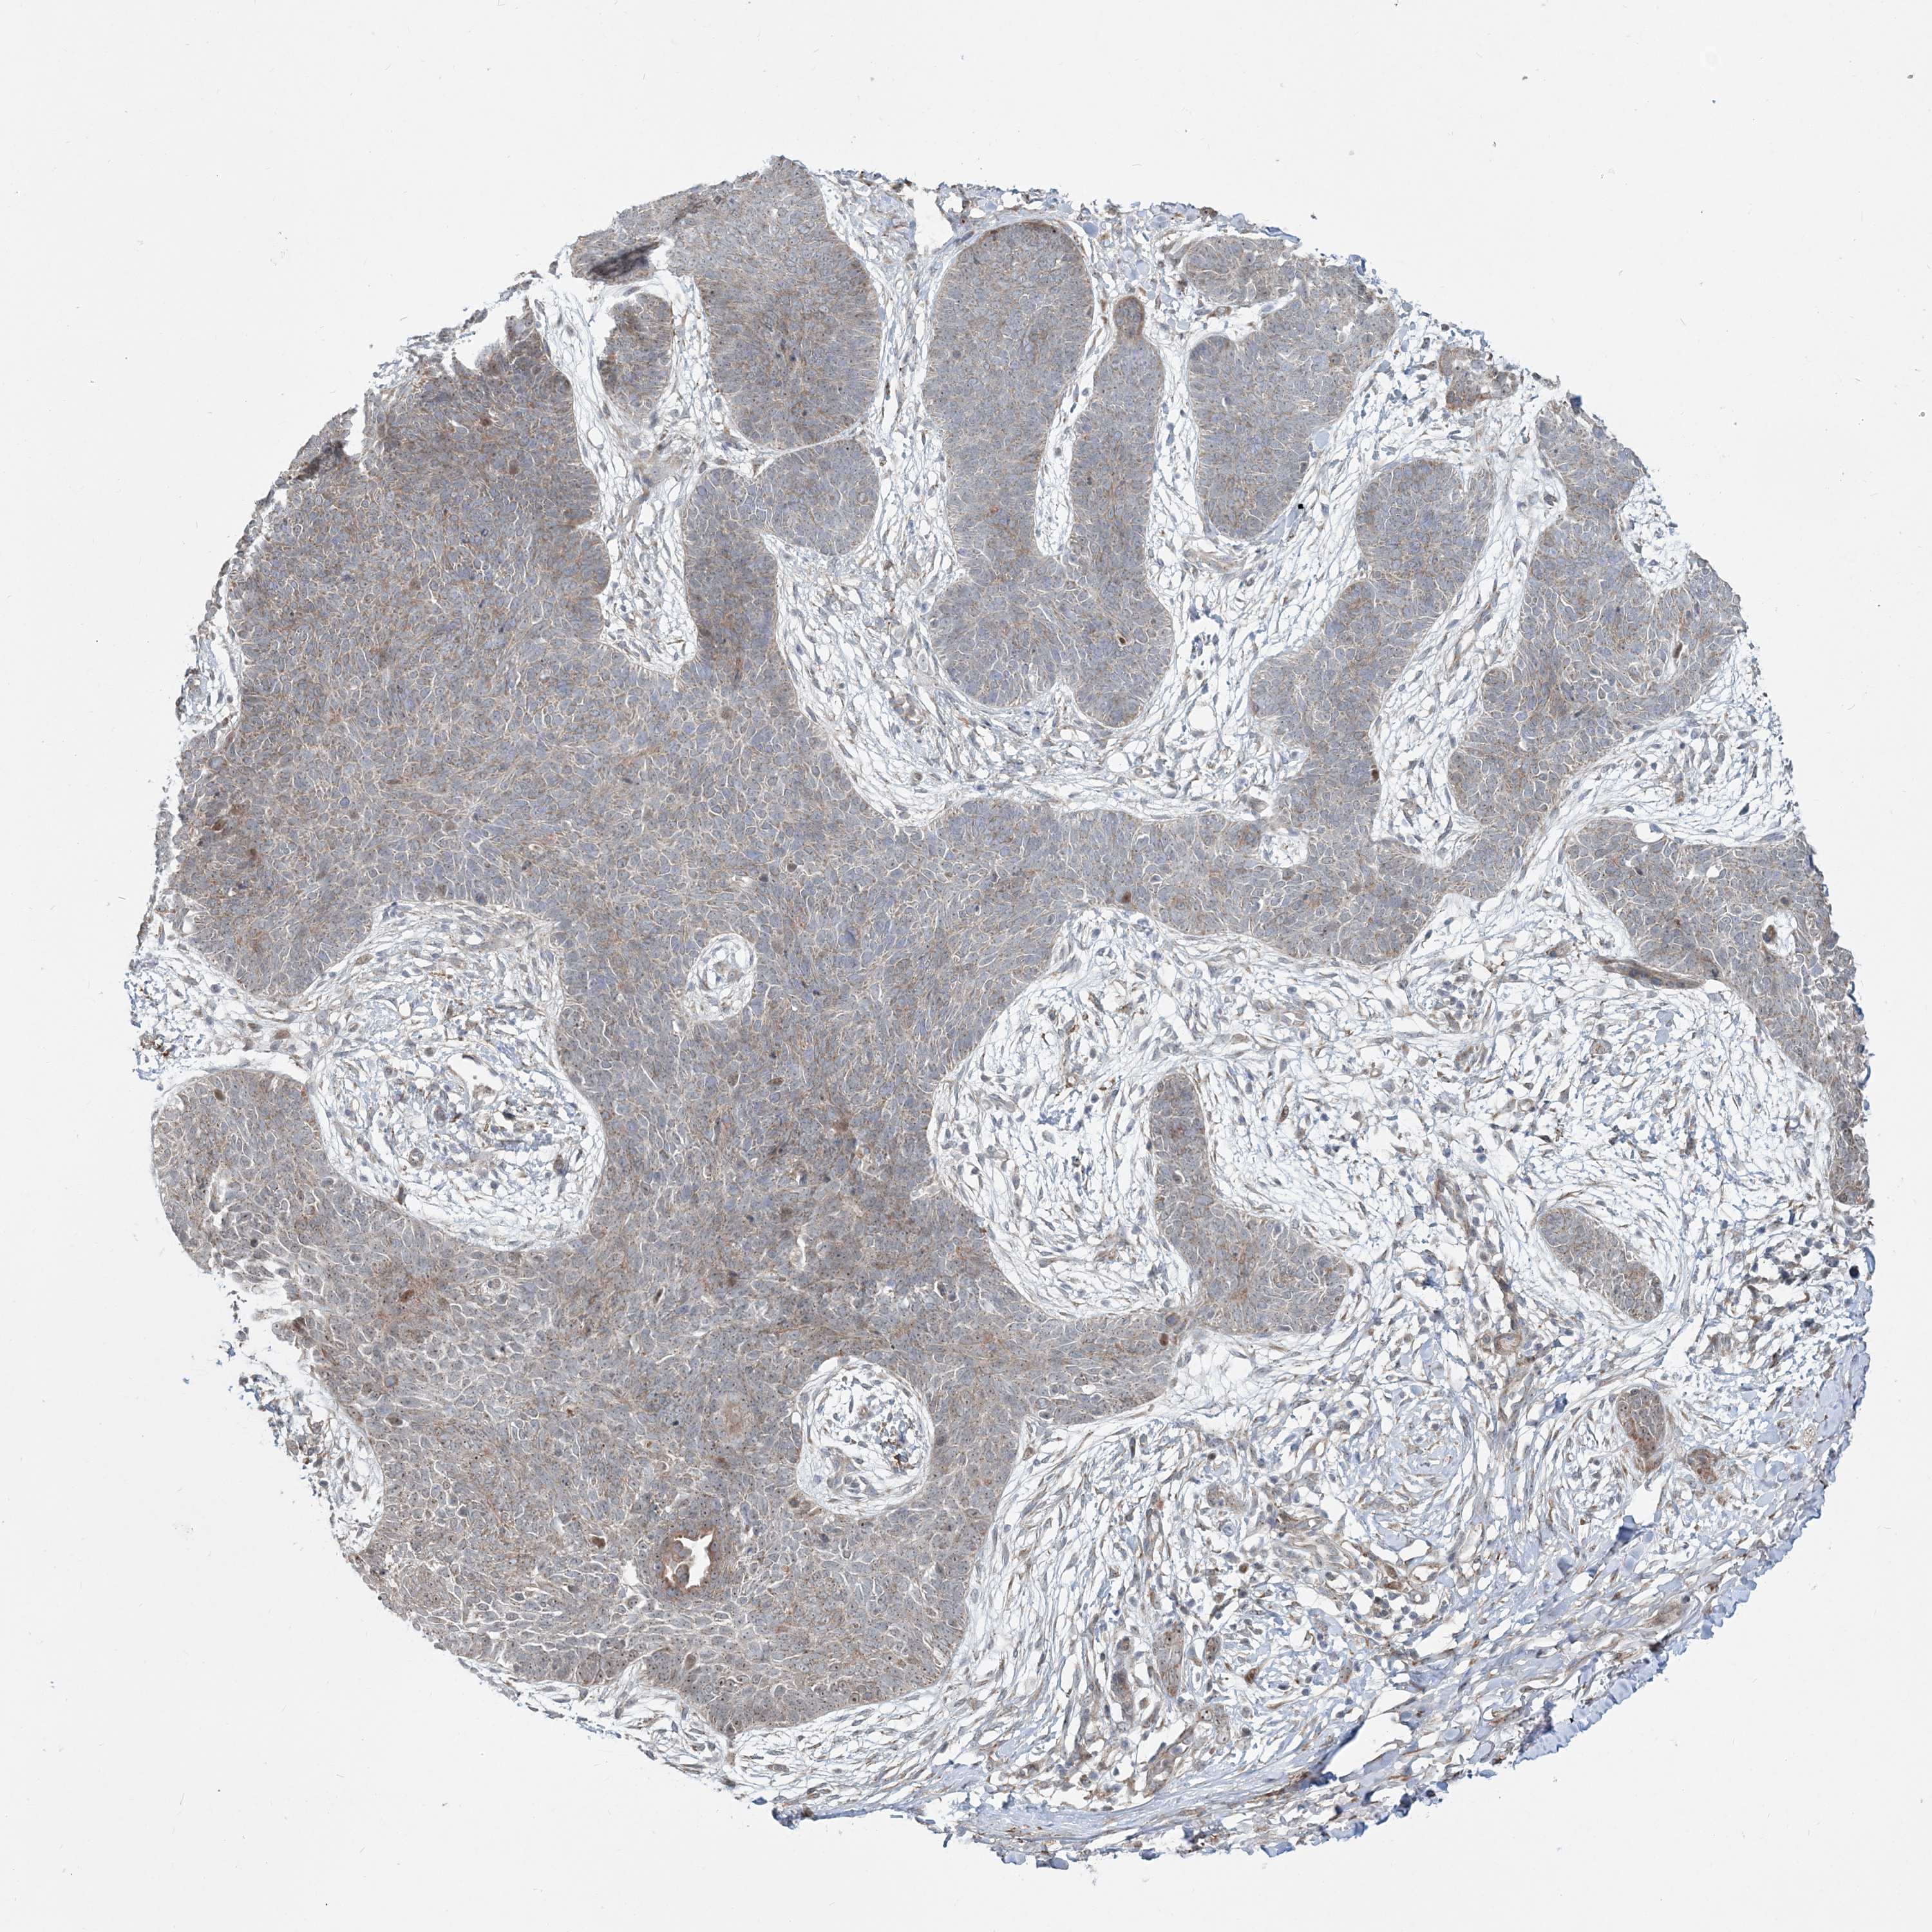

SKIN CANCER - Protein expressioni

A mouse-over function shows sample information and annotation data. Click on an image to view it in a full screen mode. Samples can be filtered based on level of antibody staining by selecting one or several of the following categories: high, medium, low and not detected. The assay and annotation is described here.

Antibody staining in the annotated cell types in the current human tissue is reported as not detected, low, medium, or high, based on conventional immunohistochemistry profiling in selected tissues. This score is based on the combination of the staining intensity and fraction of stained cells.

Each image is clickable and will lead to virtual microscopy that enables deeper exploration of all samples and also displays staining intensity scores, fraction scores and subcellular localization as well as patient and tissue information for each sample.

Antibody HPA036508

Staining

High

Medium

Low

Not detected

Intensity

Strong

Moderate

Weak

Negative

Quantity

>75%

75%-25%

<25%

None

Location

Nuclear

Cytoplasmic/membranous

Cytoplasmic/membranous,nuclear

Basal cell carcinoma

Squamous cell carcinoma, NOS